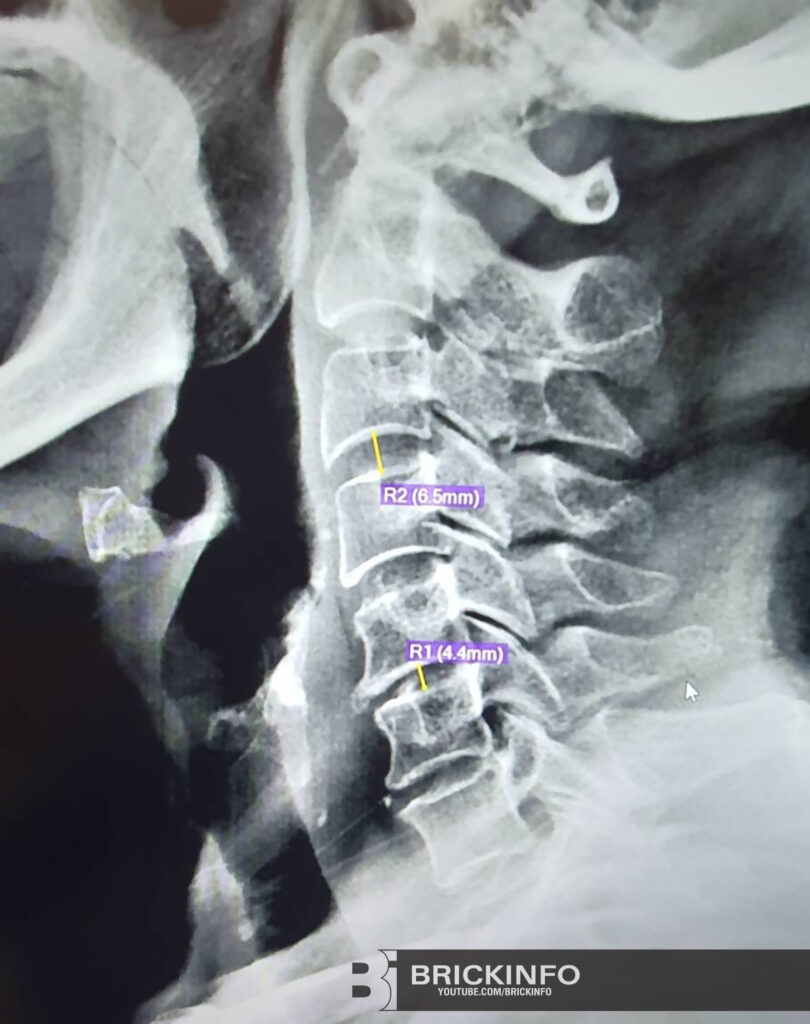

ในอดีต จะตรวจพบเจอโรคนี้ ในกลุ่มคน อายุ 40-50 ปีขึ้นไป โดยสาเหตุหลักๆ เป็นจากความเสื่อมตามอายุ แต่ในโลกปัจจุบัน พฤติกรรมการใช้ชีวิตของคนเปลี่ยนไป มีการใช้โทรศัพท์มือถือ แท็บเล็ต คอมพิวเตอร์ มากขึ้น เป็นส่วนหนึ่งของชีวิตประจำวัน ทำให้มีพฤติกรรมก้มๆเงยๆ คอ มากกว่าปกติ ทำให้ หมอนรองกระดูกคอทำงานหนัก เร่งให้เกิดความเสื่อมเร็วขึ้น จึงทำให้ในปัจจุบัน พบโรคนี้ในคนหนุ่มสาวมากขึ้น การตรวจวินิจฉัยยืนยันโรค แพทย์จะส่งตรวจเอกซเรย์เพิ่มเติม เพื่อเป็นการยืนยัน โดยมักจะพบ หินปูนเกาะบริเวณกระดูกคอ อาจตรวจพบความสูงหมอนรองกระดูกคอ ทรุดตัวลง เมื่อเทียบกับหมอนรองกระดูกที่ปกติ